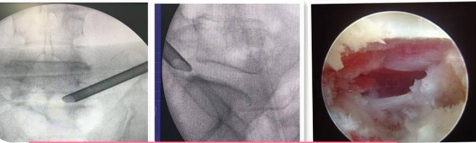

椎間孔鏡技術:

利用椎間孔鏡從患者腰椎側方或者后方進入達到椎間盤突出或者其他病變部位,用專用工具將突出(脫出)的椎間盤組織或病變取出(去除)從而達到治療椎間盤突出或者椎管狹窄的目的。它的優勢在于:局部麻醉、微創、切口小(僅約7mm)出血少,恢復快(第二天即可佩戴硬腰圍下地)及療效好。

539650c2baae42ea976bd4bf6a4f7947.Png